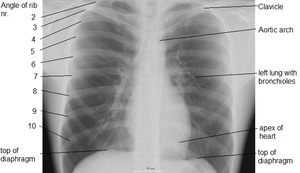

وهو عضلة مخططة ( اي من النو ع الذي تستطيع ان تتحكم به اراديا ) لكنه يمكن ان يتحرك بدون ان تتحكم به اراديا ايضا . فممكن ان تتحكم بسرعة التنفس فتبعث الاوامر من منطقة الحركة في قشرة المخ ، وعندما تنام فان الاروامر تستمر من ال Medulla و Pons وهي مراكز التنفس في الدماغ . تلتصق عضلة الحجاب الحاجز بالسطح الداخلي من الاضلاع الستة السفلى ، والفقرات الاثنين او الثلاثة الصدرية العليا ، واسفل عظم الصدر الامامي Xyphoid Process و Lumbosacral Ligament . تصعد الياف العضلة إلى فوق ثم تلتحم مع بعضهما في رباط في الوسط The Central Tendonوتكون في الجهة اليمنى اعلى من الجهة اليسرى ( المكان الذي تغطي فيه الكبد ) ويكون هذا الاختلاف واضحا في اشعة الصدر . عندما يأخذ المرء نفسًا يتقلص الحجاب الحاجز ويتحرك إلى أسفل، وهذا يزيد مساحة الفراغ في الصدر. وفي الوقت ذاته، فإن العضلات المرتبطة بالأضلاع تجعل الأضلاع تتحرك نحو الخارج. وهذا من شأنه أن يوسع الصدر ويخلق مع حركة الحجاب الحاجز باتجاه الأسفل فراغًا بسيطًا في الصدر. ويجعل هذا الفراغ الهواء يدخل الرئتين عبر القصبة الهوائية، وهذا العمل ىُدعى التنفس أو الشهيق. وفي أثناء الزفير يخرج الهواء من الرئتين، عندما ينبسط الحجاب الحاجز وعضلات الأضلاع. وعندما يتنفس المرء بشكل طبيعي، يكون الزفير في حالة سلبية والعضلات دون عمل. وتحتوي الرئة المتوسعة على ألياف مرنة كانت قد تمددت أثناء التنفس. وهذا النسيج المرن يشبه في سلوكه الخيوط المطاطية المشدودة، ويجعل الرئة تتقلص كالبالون المنكمش. وهذا يطرد الهواء خارج الصدر، وتصغر الرئة حتى تصل إلى الحجم الذي بدأ فيه التنفس. ولاتفرغ الرئتان بشكل كامل أثناء الزفير لأن جدار الصدر يبقيها في حالة متمددة جزئيًا. ويكون الزفير نشطًا أثناء التنفس الشديد الذي يحدث أثناء التمارين الرياضية. وهناك مجموعة أخرى من عضلات الأضلاع تساعد في جعل الصدر أصغر، كما أن العضلات في جدار البطن تتقلص لتدفع بالأعضاء البطنية إلى أعلى أمام الحجاب الحاجز، وتساعد بذلك على إخراج الهواء من الرئتين.